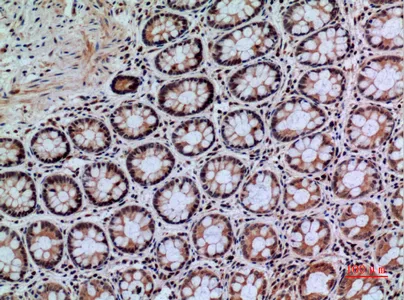

CD66e Rabbit Polyclonal Antibody

Cat: APRab08434

Size1:50μl Price1:$118

Size2:100μl Price2:$220

Size3:500μl Price3:$980

Size2:100μl Price2:$220

Size3:500μl Price3:$980